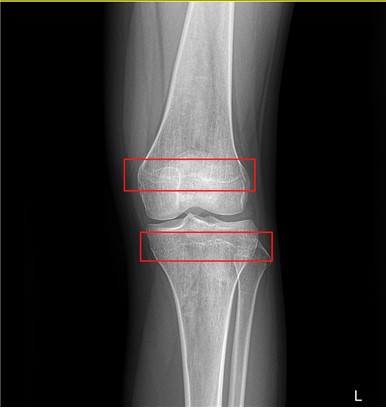

[사진 2. 만 15세 여자 어린이의 무릎 성장판 x-ray]

위의 사진 2에서는 그와 반대로 붉은 네모 안이 성장판 부분으로

검은 선이 희미하고 오히려 흰 색선이 있는 듯이 보이는 것은

이미 성장판이 많이 닫혀가고 있음을 알 수 있습니다.